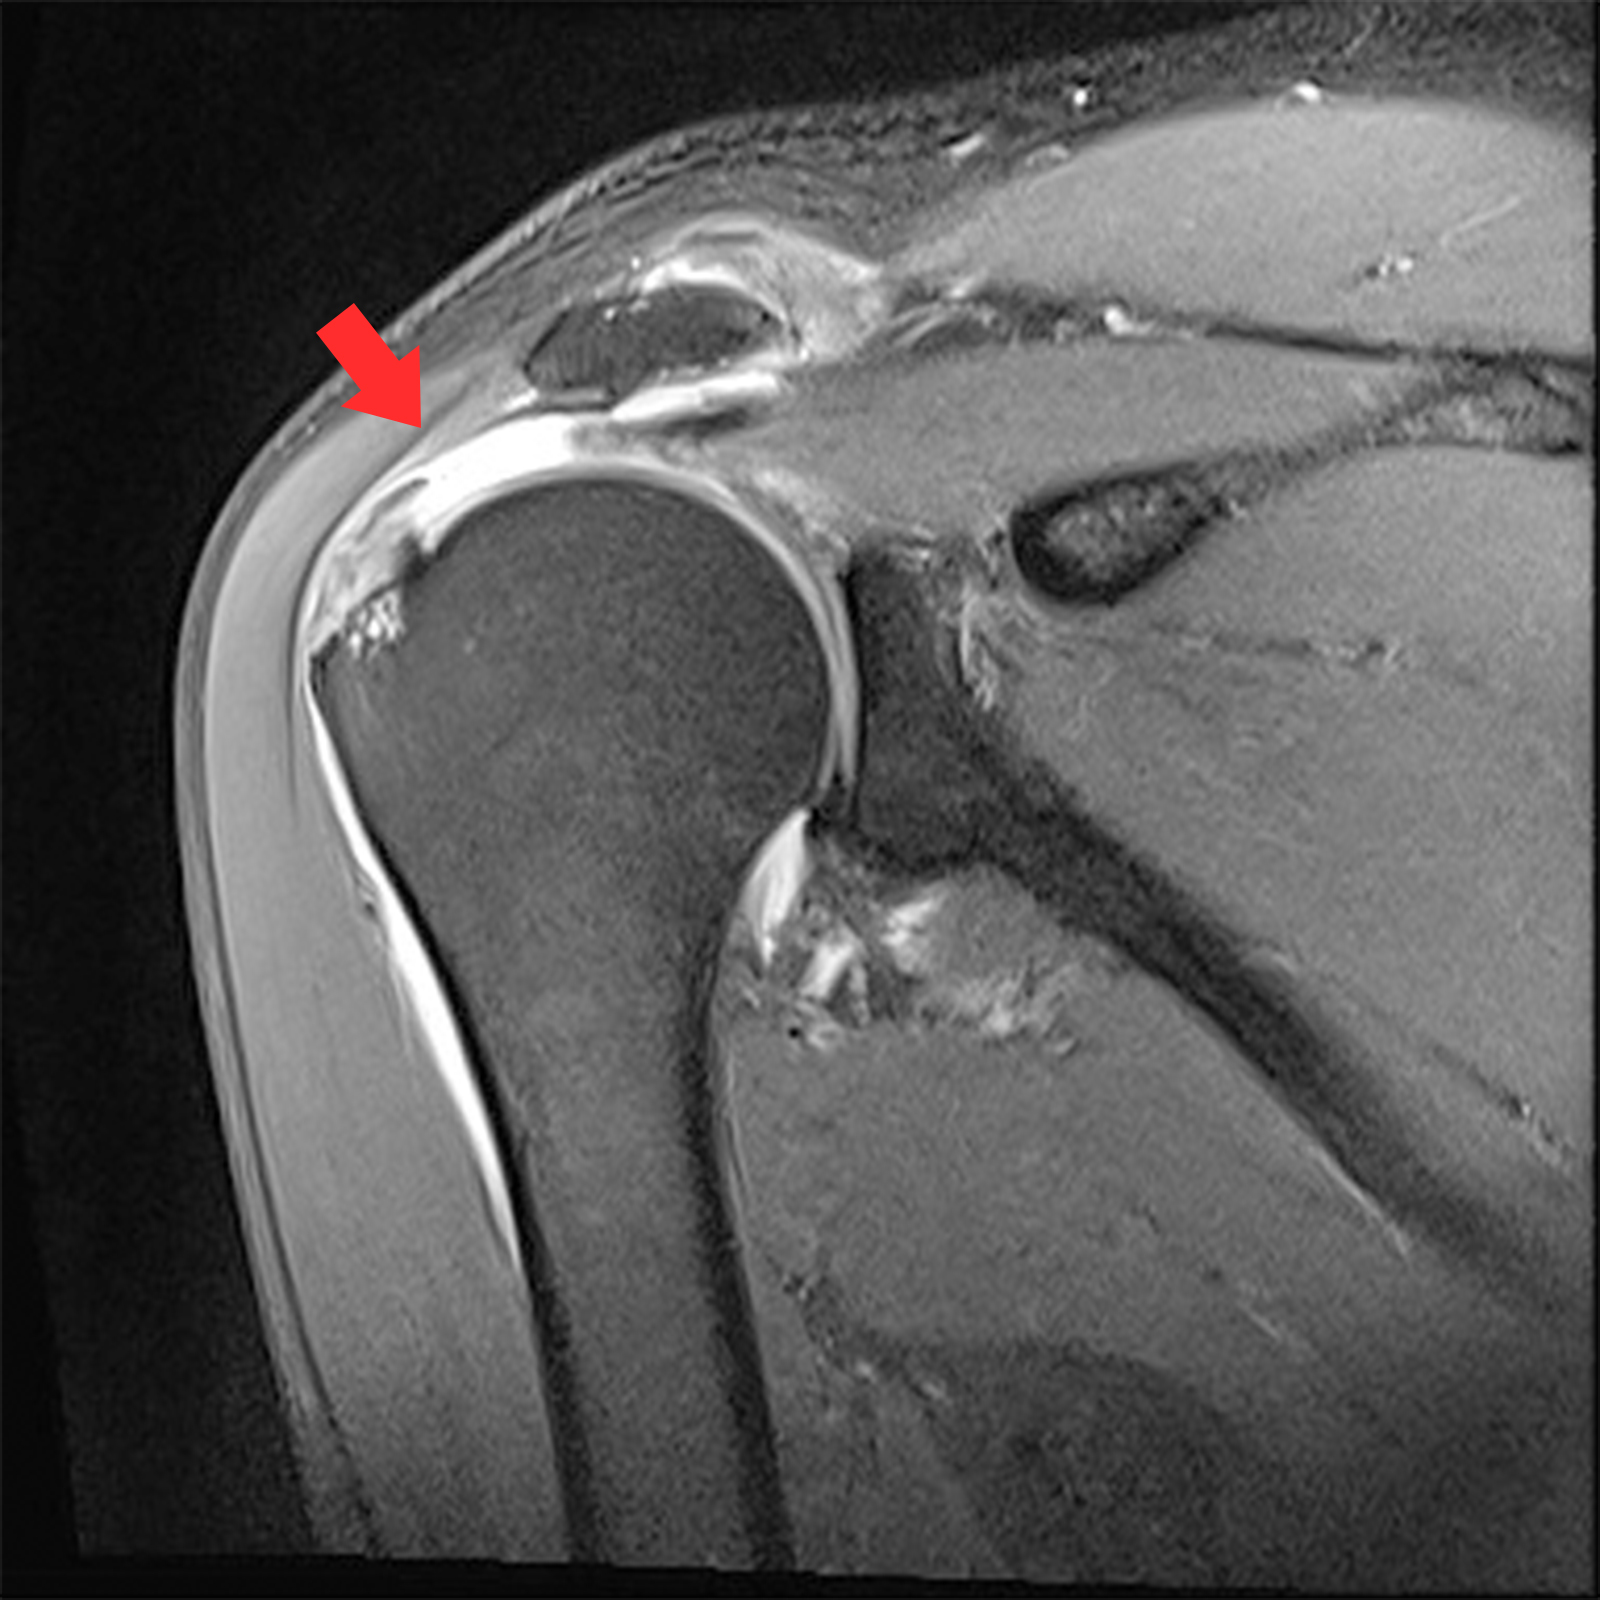

MRI 촬영시 정상적인 어깨의 경우 회전근개가 까맣게 나타나지만, 파열된 경우 하얗게 보여짐

관절내시경 수술 후

회전근개를 다듬고 봉합해준 모습

2022.06.17